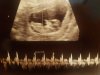

• 20200622_155537.jpg

20200622_155537.jpg

1,6 MB · Wyświetleń: 116